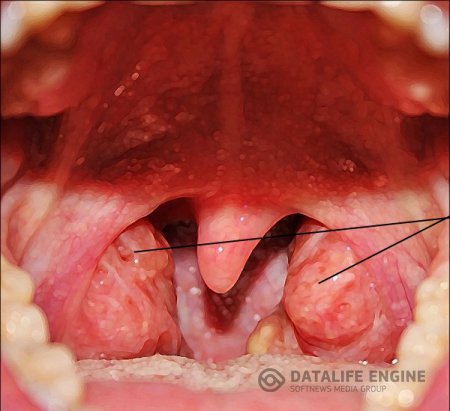

Аденоиды - лечение народными средствами

При лечение аденоидов таблетки неэффективны, капли также неэффективны. Народная медицина советует использовать, для лечения аденоидов, полоскание носа и носоглотки различными отварами и настоями.